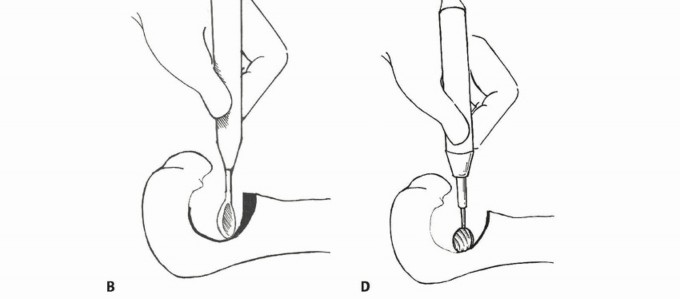

الكشط والعلاج المساعد (Curettage and Adjuvant Therapy):

تُستخدم عادة لأورام العظام الحميدة، حيث يتم كشط الورم من داخل العظم، ثم يتم استخدام مواد مساعدة مثل الفينول أو النيتروجين السائل أو الكي الكهربائي لتدمير أي خلايا ورمية متبقية.

5. العلاج بالتبريد (Cryoablation): النهج الثوري

يُعد العلاج بالتبريد، خاصةً بتقنية الصب المباشر بالنيتروجين السائل، ثورة حقيقية في علاج أورام العظام، حيث يقدم بديلاً فعالاً وآمنًا للجراحات الكبرى، مع الحفاظ على الطرف المصاب ووظيفته. يعتمد هذا النهج على تدمير الخلايا السرطانية عن طريق تعريضها لدرجات حرارة منخفضة جدًا، مما يؤدي إلى تجميدها وموتها.

آلية عمل العلاج بالتبريد:

تتمثل الفكرة الأساسية في تجميد الخلايا السرطانية وتذويبها بشكل متكرر. عند تجميد الخلايا، تتكون بلورات الثلج داخل وخارج الخلايا، مما يؤدي إلى:

تقنية الصب المباشر بالنيتروجين السائل: تفاصيل الإجراء

تعتبر تقنية الصب المباشر بالنيتروجين السائل (Direct Pouring Liquid Nitrogen Technique) في العلاج بالتبريد لأورام العظام من التقنيات المتقدمة التي تتطلب دقة عالية وخبرة جراحية متخصصة. يفضل الأستاذ الدكتور محمد هطيف هذه التقنية نظرًا لفعاليتها في تحقيق تجميد عميق وشامل للورم، مع الحفاظ على الأنسجة السليمة المحيطة.

التحضير قبل الإجراء:

- التقييم الشامل: يقوم الدكتور هطيف بإجراء تقييم سريري دقيق، ومراجعة التاريخ المرضي للمريض، وإجراء الفحوصات التصويرية اللازمة (الأشعة السينية، الرنين المغناطيسي، الأشعة المقطعية، ومسح العظام) لتحديد حجم الورم وموقعه وعلاقته بالهياكل الحيوية المحيطة.